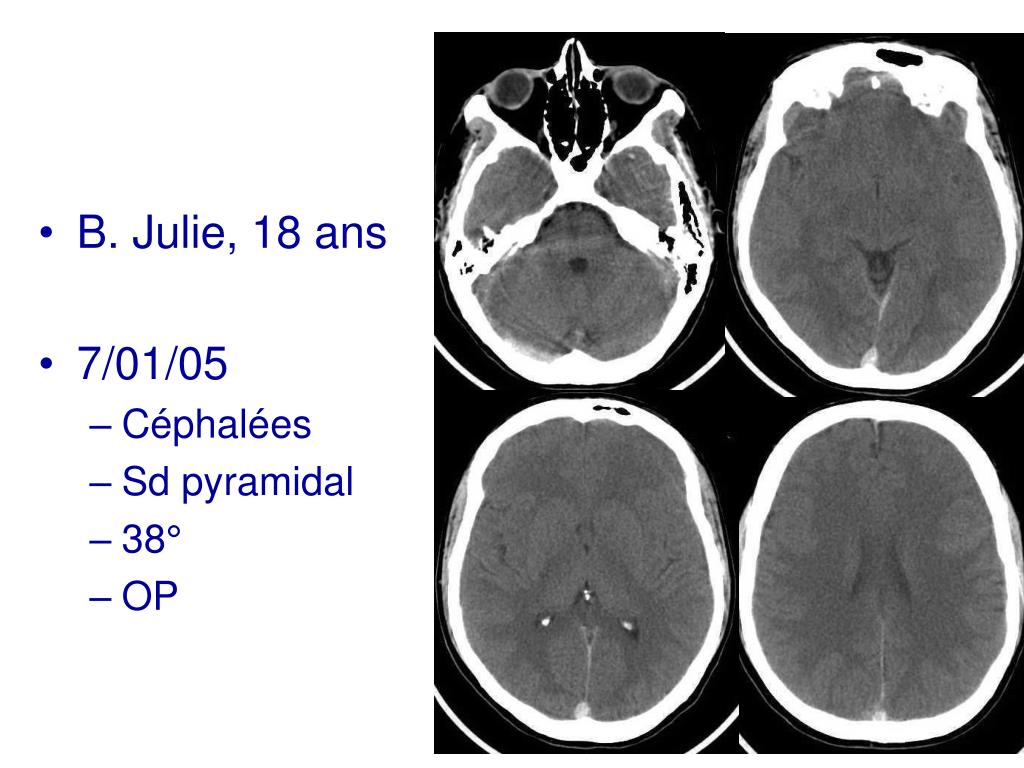

37. B. Julie, 18 ans • 7/01/05 • Céphalées • Sd pyramidal • 38° • OP

38. diagnostic J7